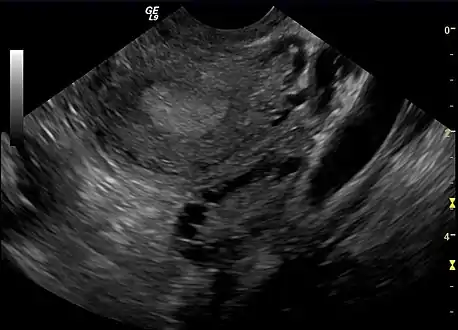

Transvaginal ultrasound scan of polycystic ovary

Polycystic ovary as seen on sonography

The syndrome acquired its most widely used name due to the common sign on ultrasound examination of multiple (poly) ovarian cysts. These "cysts" are in fact immature ovarian follicles. The follicles have developed from primordial follicles, but this development has stopped ("arrested") at an early stage, due to the disturbed ovarian function. The follicles may be oriented along the ovarian periphery, appearing as a 'string of pearls' on ultrasound examination.[79]

- Gynecologic ultrasonography, specifically looking for small ovarian follicles. These are believed to be the result of disturbed ovarian function with failed ovulation, reflected by the infrequent or absent menstruation that is typical of the condition. In a normal menstrual cycle, one egg is released from a dominant follicle – in essence, a cyst that bursts to release the egg. After ovulation, the follicle remnant is transformed into a progesterone-producing corpus luteum, which shrinks and disappears after approximately 12–14 days. In PCOS, there is a so-called "follicular arrest"; i.e., several follicles develop to a size of 5–7 mm, but not further. No single follicle reaches the preovulatory size (16 mm or more). According to the Rotterdam criteria, which are widely used for diagnosis of PCOS,[10] 12 or more small follicles should be seen in a suspect ovary on ultrasound examination.[21] More recent research suggests that there should be at least 25 follicles in an ovary to designate it as having polycystic ovarian morphology (PCOM) in women aged 18–35 years.[88] The follicles may be oriented in the periphery, giving the appearance of a 'string of pearls'.[89] If a high-resolution transvaginal ultrasonography machine is not available, an ovarian volume of at least 10 ml is regarded as an acceptable definition of having polycystic ovarian morphology. rather than follicle count.[88]